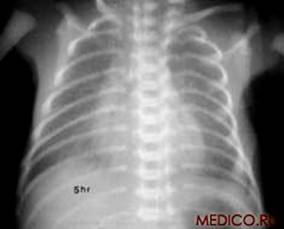

7. Легкие живого человека

А)                                                    Б)

Рис 1. Рентгенограммы легких: а) взрослого мужчины; б) ребенка.

При рентгенологическом исследовании грудной клетки ясно видны два светлых «легочных поля», по которым судят о легких, так как вследствие наличия в них воздуха они легко пропускают рентгеновские лучи и дают просветления. Оба легочных поля отделены друг от друга интенсивной срединной тенью, образуемой грудиной, позвоночником, сердцем и крупными сосудами. Эта тень составляет медиальную границу легочных полей; верхняя и латеральная границы образованы ребрами. Снизу находится диафрагма.

Верхняя часть легочного поля пересекается с ключицей, которая отделяет надключичную область от подключичной. Ниже ключицы на легочное поле наслаиваются пересекающиеся между собой передние и задние части ребер. Они располагаются косо: передние отрезки – сверху вниз и медиально; задние – сверху вниз и латерально. Хрящевые части передних отрезков ребер при рентгеновском исследовании не видны. Для определения различных пунктов легочного поля пользуются промежутками между передними отрезками ребер (межреберья).

Собственно легочная ткань видна в светлых ромбовидных межреберьях. В этих местах виден сетевидный или пятнистый рисунок, состоящий из более или менее узких тяжеобразных теней, наиболее интенсивных в области корней легких и постепенно убывающих в своей интенсивности от срединной тени сердца к периферии легочных полей. Это так называемый легочный рисунок. По обе стороны тени сердца на протяжении передних отрезков II – V ребер располагаются интенсивные тени корней легких. От тени сердца они отделены небольшой тенью главных бронхов. Тень левого корня несколько короче и уже, так как она больше прикрывается тенью сердца, чем справа.

Анатомической основой тени корней и легочного рисунка является сосудистая система малого круга кровообращения – легочные вены и артерии с радиарно отходящими от них ветвями, рассыпающимися в свою очередь на мелкие веточки. Лимфатические узлы в норме не дают тени.

Анатомический субстрат легочного рисунка и теней корней особенно ясно заметен при томографии (послойной рентгенографии), которая дает возможность получить снимки отдельных слоев легкого без наслоения на легочное поле ребер. Легочной рисунок и корневые тени есть симптом нормальной рентгеновской картины легких в любом возрасте, включая и ранний детский. При вдохе видны просветления, соответствующие плевральным синусам.

Рентгенологический метод исследования позволяет видеть изменения в соотношениях органов грудной клетки, происходящие при дыхании. При вдохе диафрагма опускается, куполы ее уплощаются, центр передвигается несколько книзу. Ребра поднимаются, межреберные промежутки делаются шире, Легочные поля становятся светлее, легочный рисунок отчетливее. Плевральные синусы «просветляются», становятся заметными. Сердце приближается к вертикальному положению. При выдохе возникают обратные соотношения.